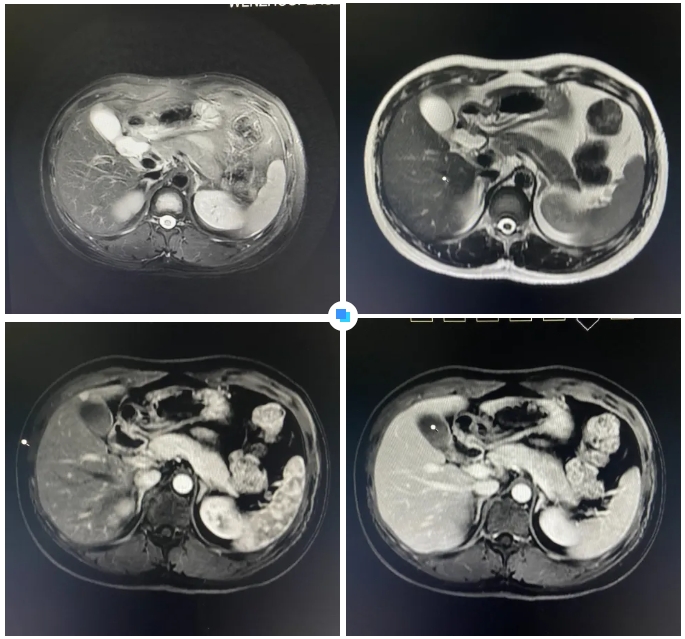

在被問到如何發(fā)現(xiàn)隱藏如此深的病灶時,和平國際醫(yī)院影像中心執(zhí)行主任侯文杰講到,該病灶在平掃T1、T2項都非常不清楚,只有彌散加權(quán)的情況下,病灶區(qū)域顯示出輕微的高信號,這一細(xì)微線索引起了他的高度關(guān)注。

隨后的增強(qiáng)核磁掃描發(fā)現(xiàn),在動脈期病灶顯著強(qiáng)化,而在門脈期明顯減退,這一特征與微小肝癌的表現(xiàn)高度吻合。